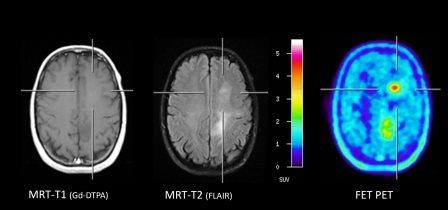

Einer der wichtigsten Aspekte bei der Diagnostik von zerebralen Gliomen ist die Erfassung der Tumorausdehnung und der Tumorareale mit der höchsten Proliferationsrate. Die Gewinnung repräsentativer

Gewebsproben ist für die Beurteilung des Tumortyps, der Prognose und die weitere Therapieplanung von entscheidender Bedeutung. Die konventionelle MRT bietet bei inhomogenen Gliomen oft nur eingeschränkte Hinweise auf die stärker proliferierenden Tumoranteile, insbesondere bei fehlender Kontrastmittelaufnahme. Die Aminosäure-PET kann bei etwa 90 % der Tumore Regionen mit erhöhter Stoffwechselaktivität nachweisen, was zu einer optimierten Planung der Biopsie beiträgt und Fehlbiopsien vermeidet (Abb. 1). Darüber hinaus bietet die Aminosäure-PET im Vergleich zur MRT in vielen Fällen eine verbesserte Darstellung der Tumorausdehnung, was z. B. zur Planung des chirurgischen Eingriffs oder der Strahlentherapie beitragen kann (Abb. 2).